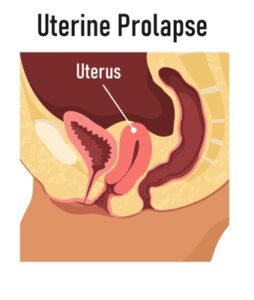

Prolapse

Post-delivery prolapse occurs when the pelvic organs (such as the bladder, uterus, or rectum) drop or bulge into the vaginal canal

due to weakened pelvic floor muscles.

- The symptoms of prolapse after childbirth can vary depending on the severity of the condition and the specific organ involved, but common symptoms include a feeling of heaviness or pressure in the pelvic region and vaginal bulging or a visible lump

- These symptoms may worsen over time, especially in the afternoon or evening